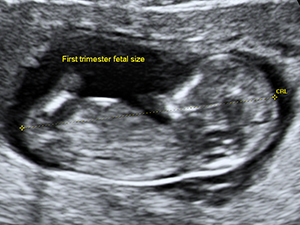

The crown-rump length of the embryo at 9 weeks

The crown-rump length of the fetus at 12 weeks